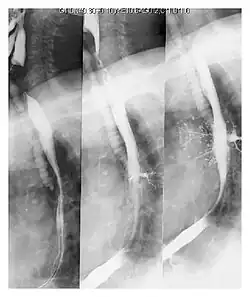

A fluoroscopic swallow study can be done in cases where dysphagia or motility disorders are thought to be the source of aspiration. Food and drink are mixed with barium contrast and monitored using x-ray to evaluate swallowing. Aspiration can be diagnosed if contrast is seen coursing below the vocal cords into the trachea.[13]